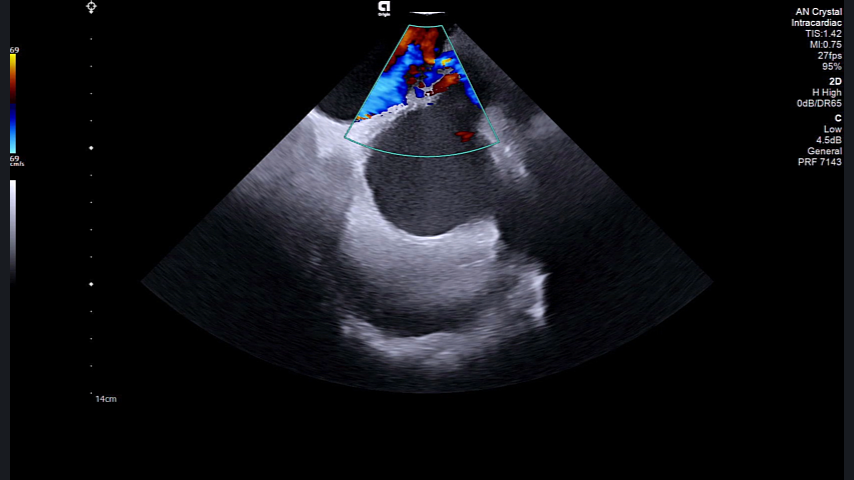

Imaging that empowers you to safely2 do more, with predictable results in real-time.

- Deeper clarity to take you further, faster, safer2: More consistent and predictable image quality

- Leak detection: Better leak visualization3

- Better resolution: Helps identify complications before they become significant, stay in flow with a system that’s designed to protect patient safety2

- Enhanced image resolution: Expands your treatment options and allows for treatment of more patients, even when contraindicated for TEE

- Accurate tissue contact and characterization: For more precise and effective treatments, like pulsed-field ablation (PFA)

- 4D ICE catheter: The volume rates you need for informed anatomical assessment and device guidance